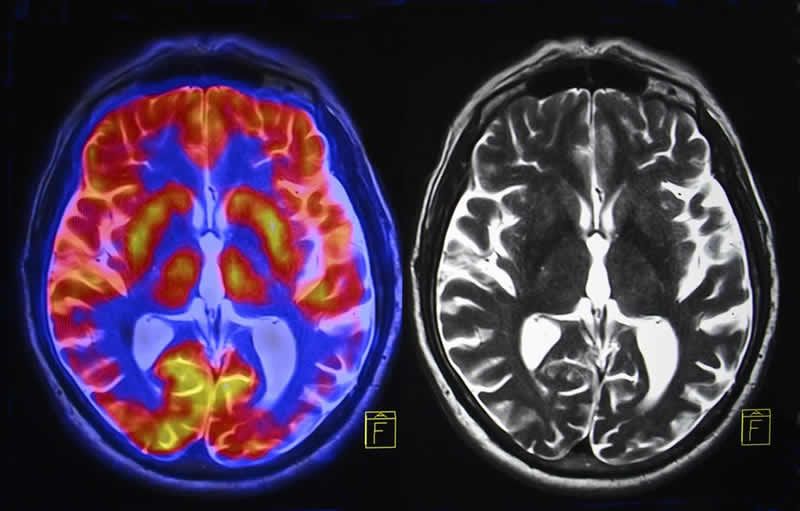

This is your brain under stress.

Chronic stress can effect hormones in the brain, including cortisol and corticotropin releasing factor (CRF). CRF coordinates fight/flight/freeze responses, related to anxiety, cognitive changes, and emotional regulation.